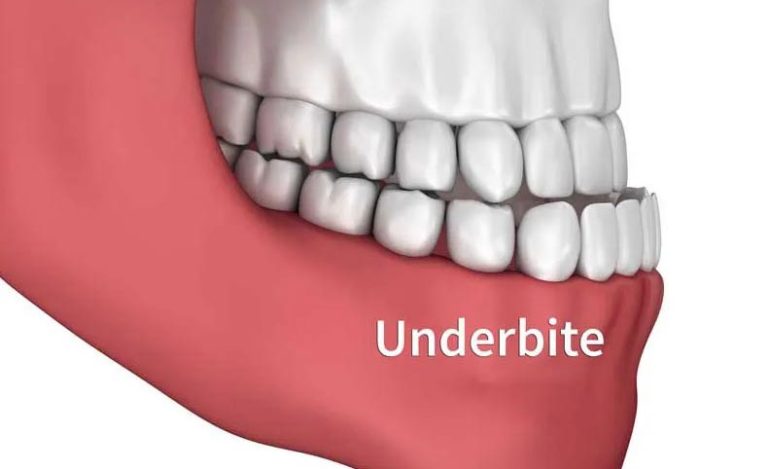

- کم برآمدگی دندان ها (دندان های پایینی که به سمت جلو کشیده شده اند)

- آندربایت (دندان های پایینی جلوتر از دندان های فوقانی)